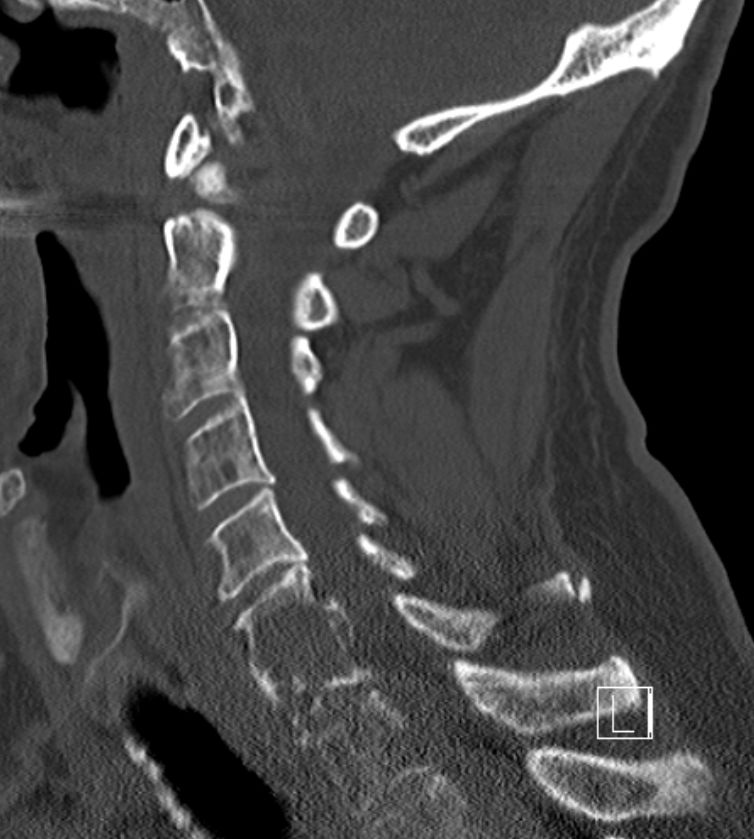

bildgebende Diagnostik